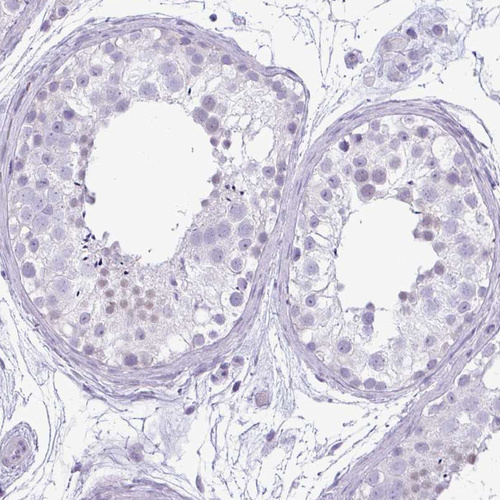

Immunohistochemistry analysis in human kidney and testis tissues using HPA036260 antibody. Corresponding CDH16 RNA-seq data are presented for the same tissues.